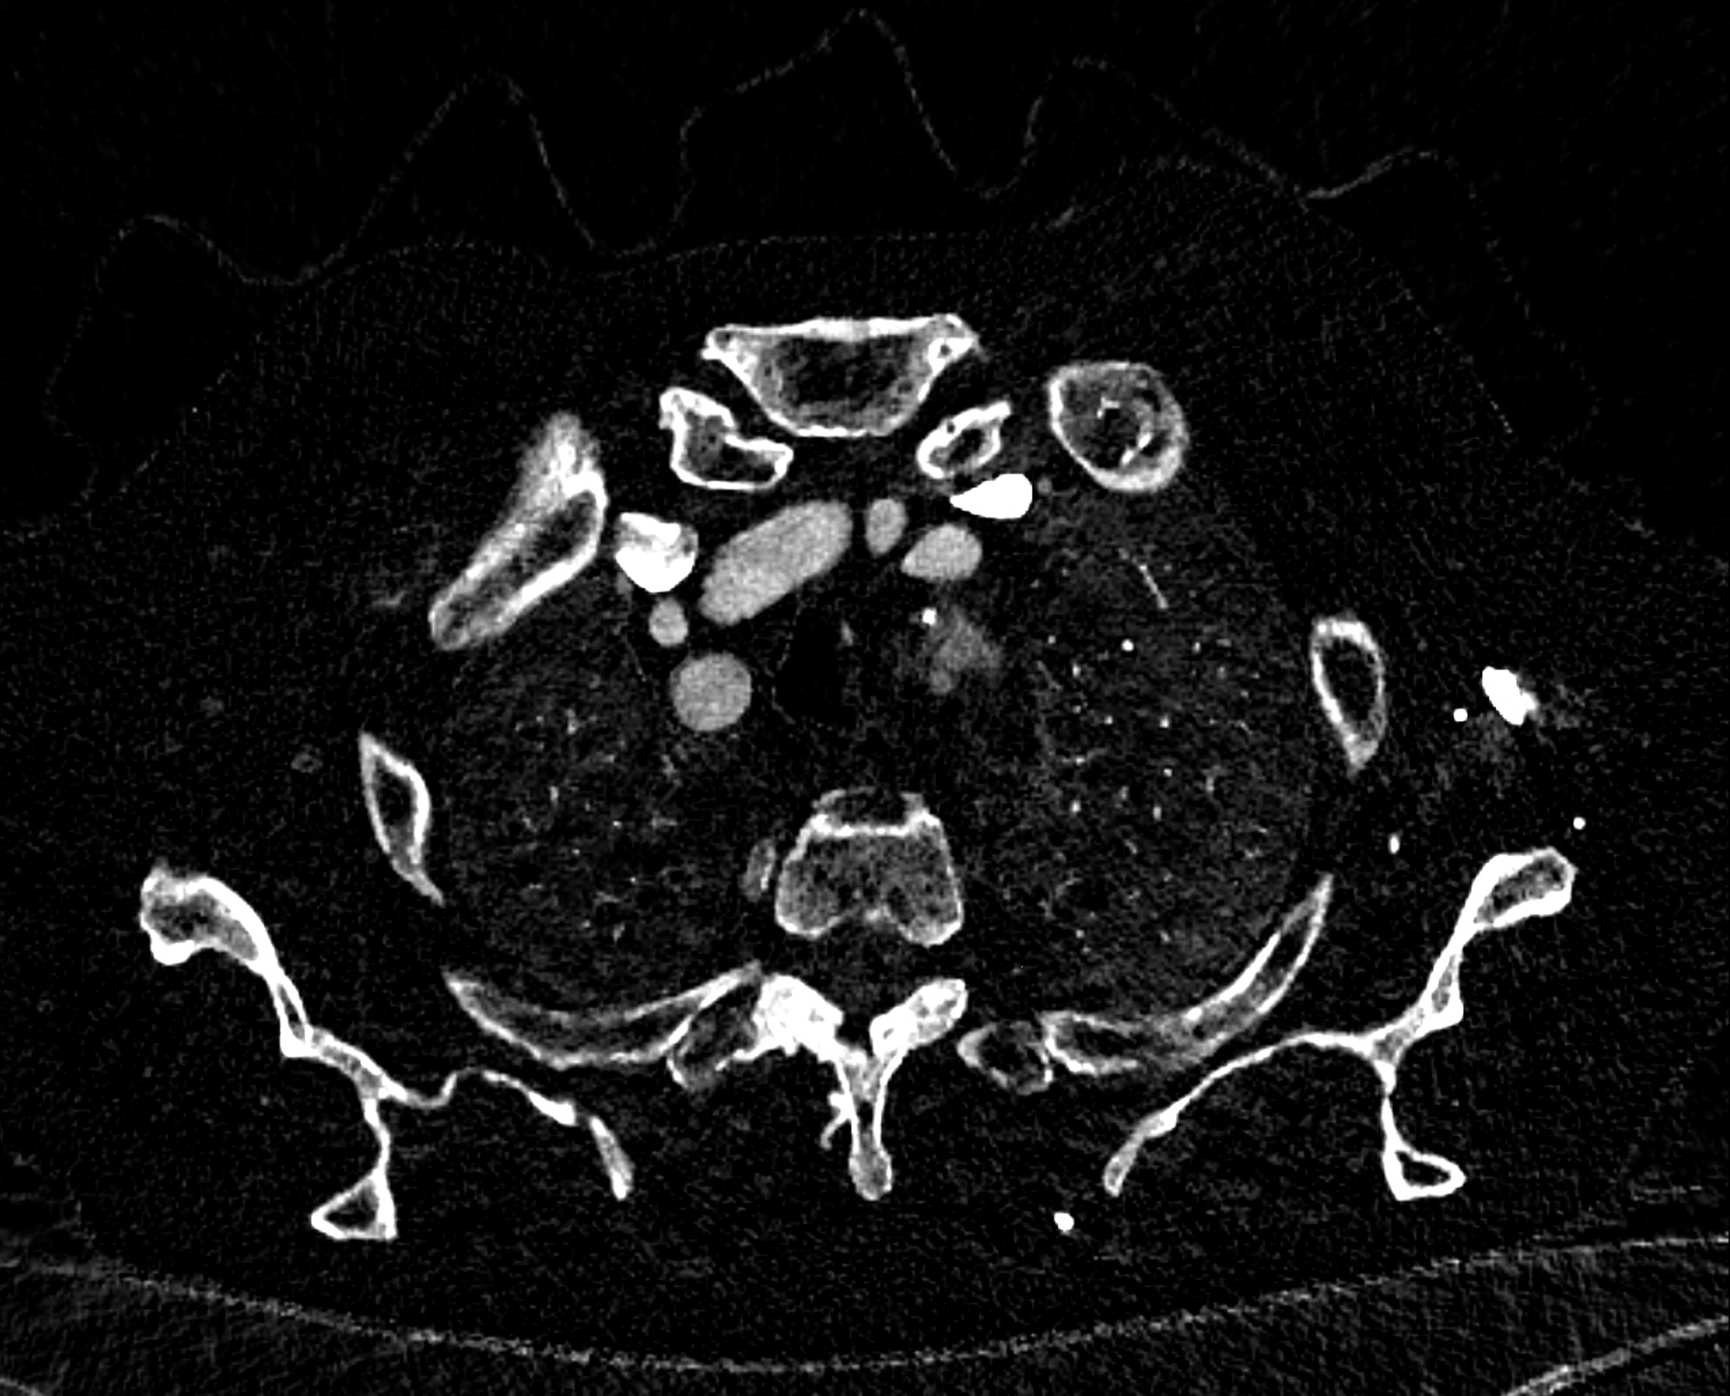

in patient chest pain, negative ECG but with elevated D-dimers was performed CTA of the chest to exclude highly suspected pulmonary embolism. No pulmonary embolism was see, but the pathology of the aortic arch and descending thoracic atorta. The images were consistent with aortic intramural hematoma type B according to the Stanford classification with incipient transformation in dissection – behind the subclavian artery, it is clear that the contrast agent is flowing into the intramural hematoma. Differentiation from wall thrombosis is facilitated by the presence of calcification in the detached intima, which is most clearly visible on virtual non-contrast imaging. The intramural hematoma itself exhibits different properties in terms of X-ray absorption. Coagulated blood is visible at the apex of the aortic arch, where it closely adjoins the area that is perfused and filled with contrast medium. There are other smaller areas filled with contrast medium at the sites of the intercostal arteries. These areas are secondary sites where the original intramural hematoma is channeled during its transformation into a classic aortic dissection.

Virtual non-contrast images help to distinguish between the intima and thus in the differential diagnosis of intramural hematoma versus wall thrombosis. Signs of fresh coagulated blood in IMH indicate bleeding into the aortic wall from the vasa vasorum. In contrast, monoenergetic images with lower energies of 40-55 keV highlight areas of intramural hematoma with active blood flow.

comparison of the the images 60, keV monoenergetic, virtual non-contrast (VNC), and iodine map images. The repercussion starts in the proximal tear of the intimate (the first three images), calcification in the intimate (next three images), tera at the level of the arising intercostal artery (last three images)